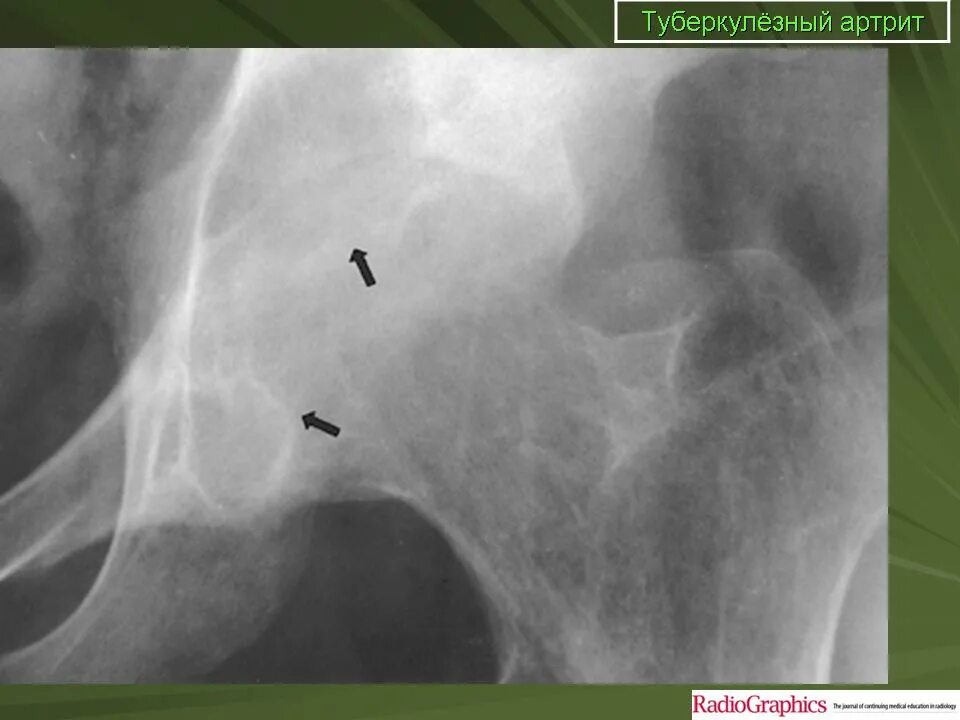

Туберкулез суставов симптомы